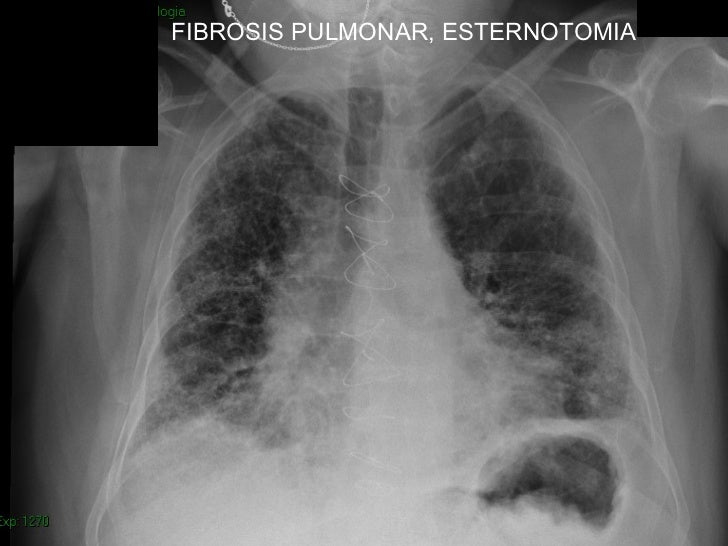

Mujer de 80 años con importante fibrosis pulmonar en rx de tórax el electrocardiograma con importante crecimiento y sibrecarga del ventrículo derecho por. La fibrosis pulmonar puede deberse a la exposición a distintas sustancias y también puede ser secundaria a otras enfermedades. La fibrosis pulmonar idiopática (fpi), la forma más común de neumonía intersticial idiopática, causa fibrosis pulmonar progresiva. Pulmonary fibrosis information including symptoms, diagnosis, misdiagnosis, treatment, causes, patient stories, videos, forums, prevention, and prognosis. Lung scars can result from illness or medical treatment, and they are permanent. Familial pulmonary fibrosis for patients. La fibrosis pulmonar es una forma de enfermedad pulmonar intersticial. It can occur in a wide range of clinical settings and can be precipitated by a multitude of causes. Find the most popular drugs, view ratings and user reviews. Hospital de la santa creu i sant pau. Medical marijuana can help relieve pulmonary fibrosis symptoms. Las enfermedades pulmonares intersticiales son un grupo de hay muchos tipos diferentes de fibrosis pulmonar. You may have pulmonary fibrosis for some time without any symptoms.